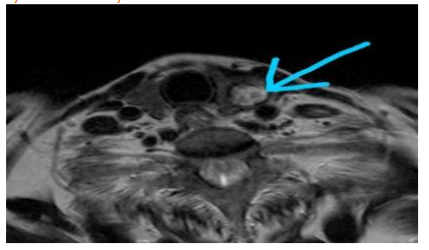

MRI Neck showed a solid ovoid nodule in the left lobe of the thyroid. Few mildly enlarged ovoid nodes in bilateral IB, II region-reactive morphology.

Well-defined solid nodule in the left lobe of the thyroid.